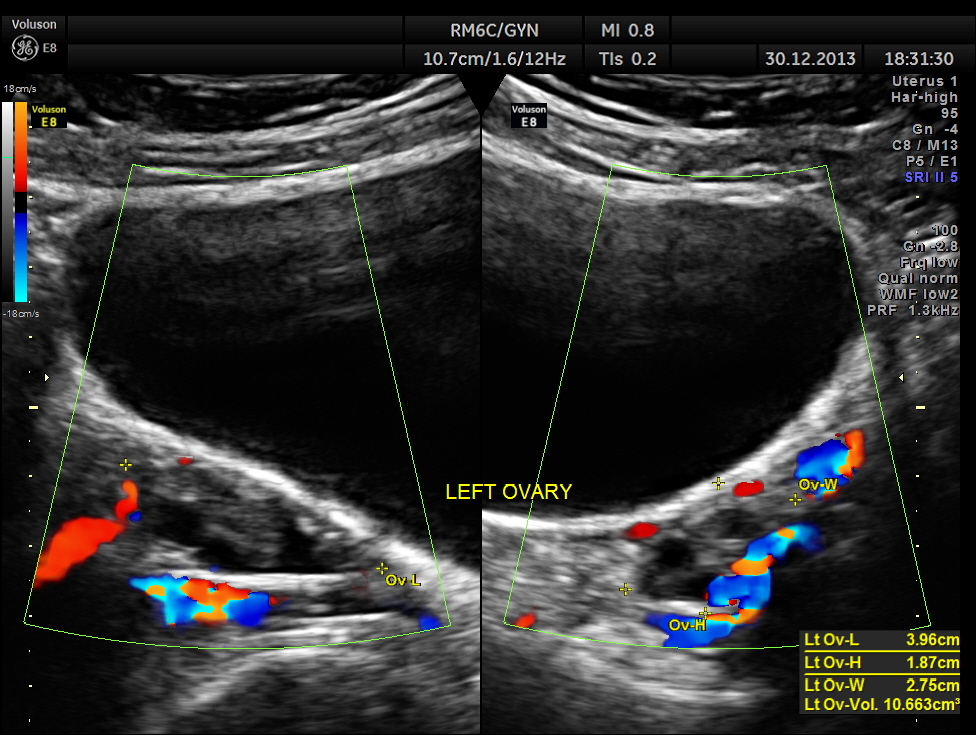

the ovaries are shown below.